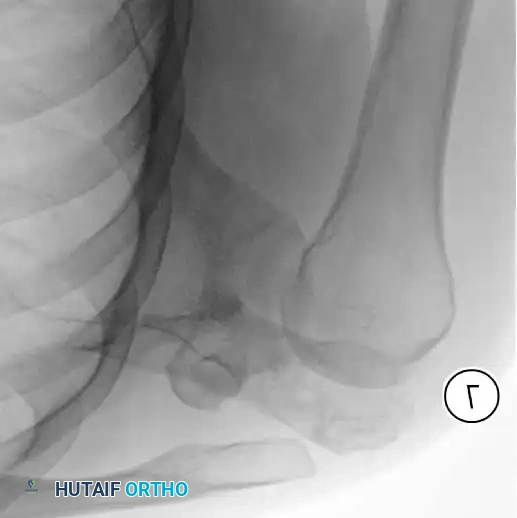

5. Pre-expansion and post-expansion radiographs are obtained to quantify the exact lengthening achieved.